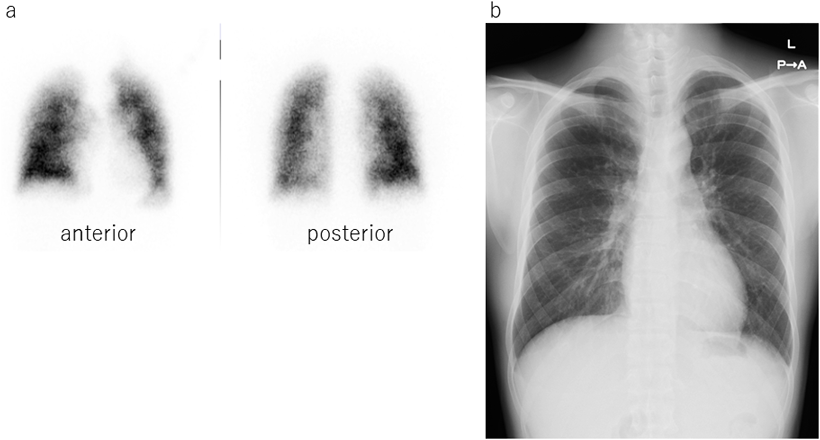

At the age of 28 years, he visited our outpatient clinic again because he recognized the severity and the poor prognosis of PAH through his university curriculum. He had no symptoms in his daily work and could easily go upstairs to 5 floors at his office. He could walk over 660 m in 6MWT and SpO2 were slightly decreased from 98% to 93% after 6MWT. His serum brain natriuretic protein was as low as below normal level. Echocardiogram revealed his right ventricle was not dilated and had preserved contraction. Chest X-ray showed mild dilatation on pulmonary trunk and lung perfusion scintigraphy showed mild diffuse patchy pattern which was typical in PAH(Fig. 2). Chest plain computed tomography could not detect abnormality. Treadmill cardiopulmonary functional test revealed SpO2 depletion from 98% to 92%.

Fig. 2 The lung perfusion scintigram and Chest X-ray images at the age of 28 years

a. Lung perfusion scintigram, b. Chest X-ray.